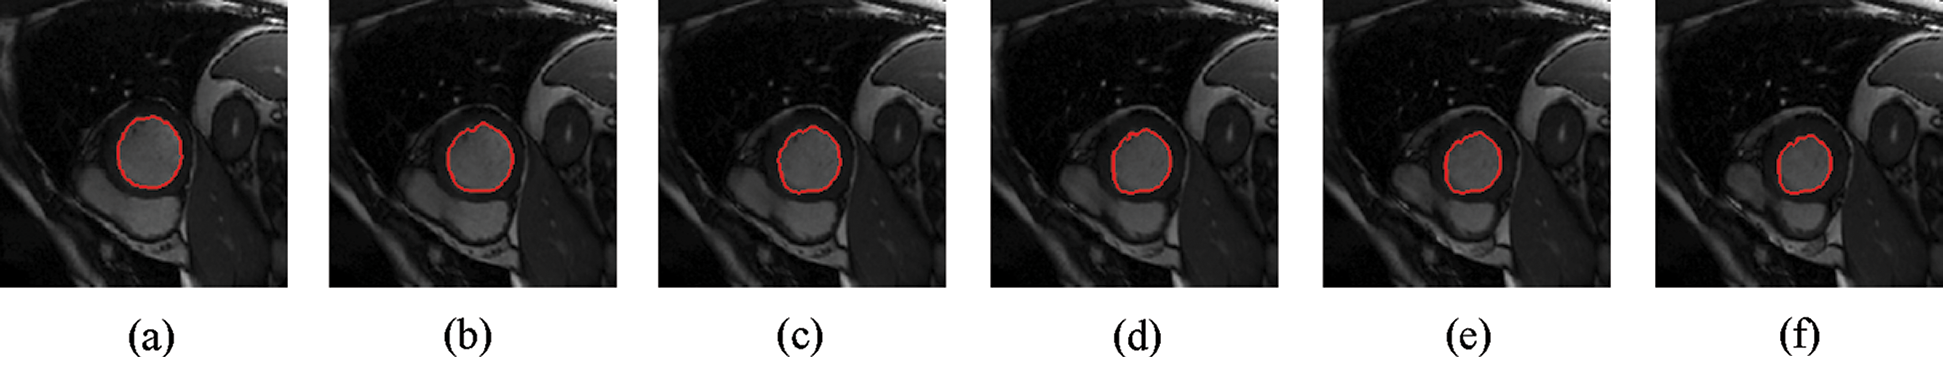

The experimental results are categorized into two distinct sections to underline both the segmentation and psoriasis lesion localization results. The presented results of this paper were obtained through using different 6 techniques to 300 sets of CVD. In this paper, multi-axis CMR database was used in three axes for 6 case studies to provide the results of various segmentation schemes. In this section, the employed techniques for studying and segmenting medical images are executed using MATLAB. Figs. 1a–1f present the Caselles segmentation technique results. These results indicate that this technique gives better results when the initialization step is suitable and the image has a high intensity gradient at the edge between the cavity and the myocardium of LV. It is also clear from the results that the blood pool segmentation depends on the boundary features. Both of Li and Bernard segmentation techniques show a wide band segmented results that are not reasonable to the blood pool segmentation as shown in Figs. 2 and 3. This is apparently visible in the Bernard segmentation technique where the segmentation partitions of each slice to bright regions and dark regions cannot separate the LV cavity from other parts of the image. The relationship between each pixel and its adjacent neighbors is considered. As it could be seen from Figs. 4a–4f, the blood pool of LV is purely delineated. That is the resulted segmented image of the Chan-Vese technique appears well-defined. Based on the obtained results, one can say Chan-Vese technique works well with homogenous regions such as cardiac images. In addition, the resulted segmented slices appear of high smoothing degree as well. The segmented images from the blood pool of LV obtained using the Lankton-Yezzi segmentation is presented in Figs. 5a–5f. As it could be seen from these figures, the quality of the segmentation process using the Lankton-Yezzi technique depends on the initialization. As it could be seen from Figs. 6a–6f, the two cycles of Shi-Karl segmentation technique produce good quality segmentation to the LV blood pool.

Figure 4: Sample results of Chan-Vese technique

Figure 5: Sample results of Lankton technique